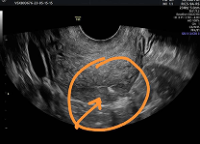

A plain abdominal radiograph demonstrated an IUCD positioned abnormally within the pelvis (Figure 1). Two-dimensional transvaginal ultrasonography re vealed a hyperechogenic focus near the uterine fun dus, raising suspicion of uterine perforation (Figure 2). Three-dimensional transvaginal imaging offered superior anatomical detail, clearly demonstrating: an empty uterine cavity, partial extrusion of the IUCD through the posterior lower uterine segment into the peritoneal cavity, and a hyperechogenic spot corres ponding to fundal trauma, likely resulting from a prior unsuccessful blind retrieval attempt (Figures 3–8). These findings confirmed uterine perforation with partial migration of the device.

Figure 5. Shows 3D image of IUD at the lower uterine segment with evidence of perforation

Figure 6. Shows the area of fundal perforation and hemoperito neum.

Figure 7. Shows the IUCD at the lower uterine segment partly extruded into the peritoneal cavity with hemoperitoneum.